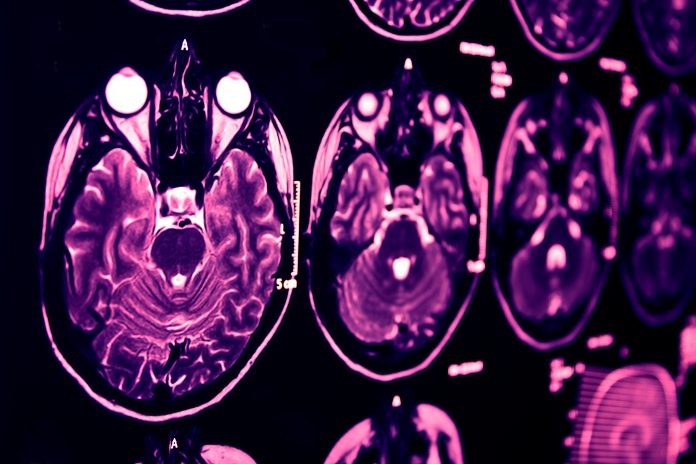

As Alzheimer’s pathology progresses, the brain loses synapses that cannot be recovered. In the early stages of the disease, the brain has sufficient excess capacity and plasticity to overcome the loss. But later, the cognitive reserve is depleted, and the brain can’t bounce back similarly. Finding a way to arrest the disease before the brain turns this corner remains an ever-urgent need.

There have been significant innovations in diagnostic tests to detect and measure the presence of these Alzheimer’s biomarkers, including cerebral spinal fluid (CSF) analysis and positron emission topography (PET) scanning. Although these tests are currently considered the gold standard for diagnosis, they are expensive and invasive. Even more problematic, 19% of CSF analysis cases result in complications.

Early detection of Alzheimer’s disease with the ViewMind test Digital health company ViewMind has developed a non-invasive, cost-effective 15-minute assessment that can detect the earliest accumulations of beta- Amyloid and Tau in brain areas first affected by Alzheimer’s pathology. The test’s findings—which tracks the digital biomarker of eye movement—correlate with results garnered from CSF testing and PET scans.

ViewMind uses medical-grade VR headsets to relay visual stimuli to a patient’s eyes, sending a signal via the optical nerve to the visual cortex. The relevant brain region is then activated, and the eyes’ phenotypical response can be linked with individual cognitive functions and the preservation of different brain regions.

When the eye movements linked to several brain regions results are considered alongside one another, a precise understanding of brain health can be gleaned. So not only is ViewMind’s test safe, non-invasive, fast, and accessible—it also provides precise and critical information about the functional impact of Alzheimer’s biomarkers.